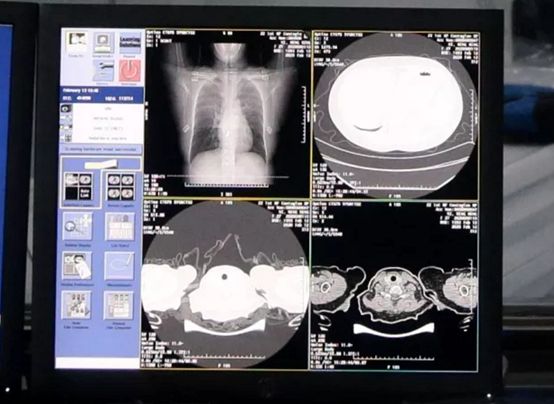

达摩院 CT 影像 AI 系统能直接算出病灶部位的占比比例,量化、预测病症的轻重程度,大幅度提升诊断效率,为患者的治疗争取宝贵时间。

AI 自动识别新冠肺炎病例 CT 胸片

「系统 20 秒内对新冠疑似患者 CT 影像做出判读,并量化病症的轻重程度,分析结果准确率达到 96%」,从华先胜嘴里跳出的数据,直观地显示着这套系统的辅助作用。